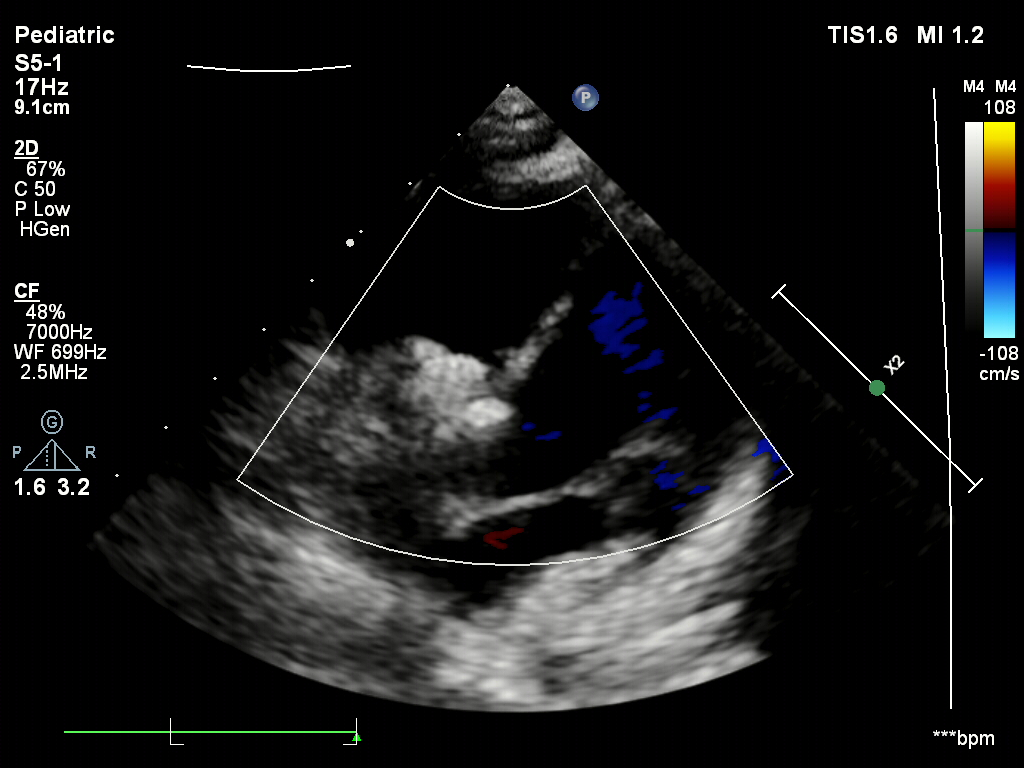

术后1个月超声

封堵器稳定夹持在室间隔两侧,无残余分流